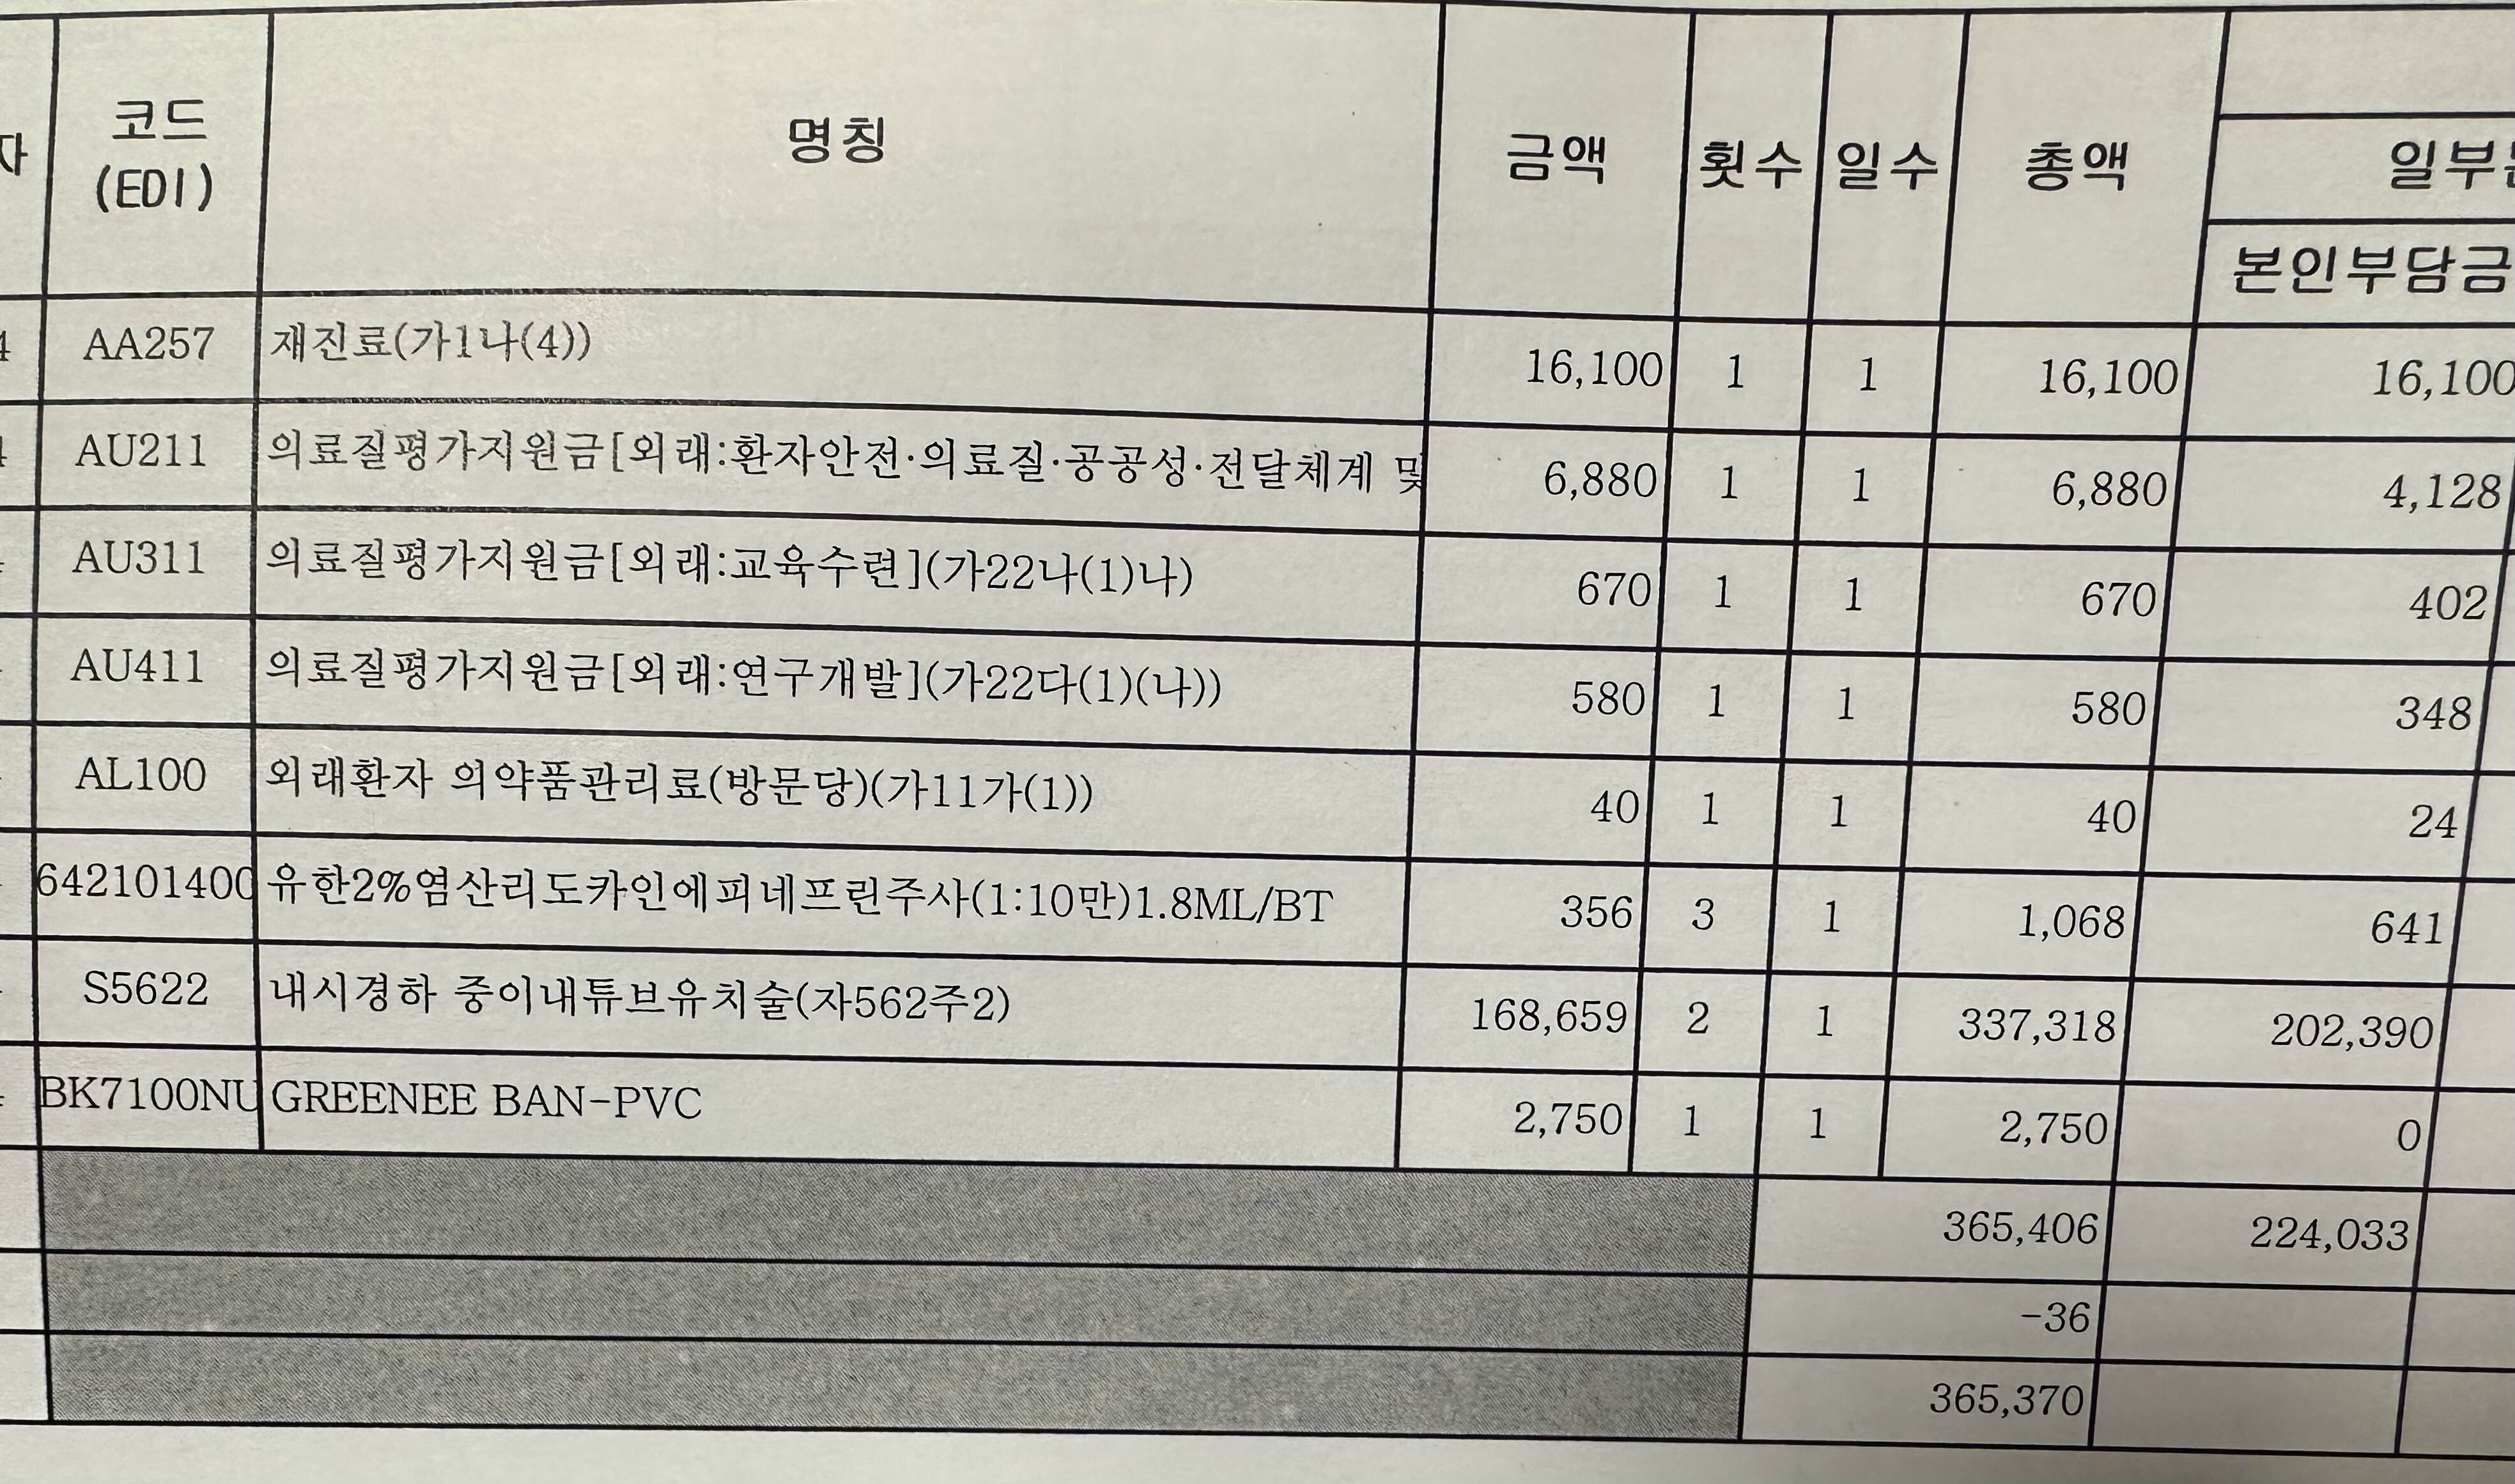

5. 고막환기관 삽입 수술의 세부내역서 입니다. 저는 양쪽 귀에 한 개씩 총 2개를 넣었습니다. 참고해 주세요.

진료비 총액에서 환자부담총액만 내면 되기때문에 저는 226,783원을 내었습니다. 사실 수술비용이나 진료비용의 경우에는 병원에 따라 다르기 때문에 이 가격이 정답이라 할 수는 없지만 그래도 금액이 엄청 많이 나오지 않는다는 사실 정도는 알 수 있는 것 같아요.